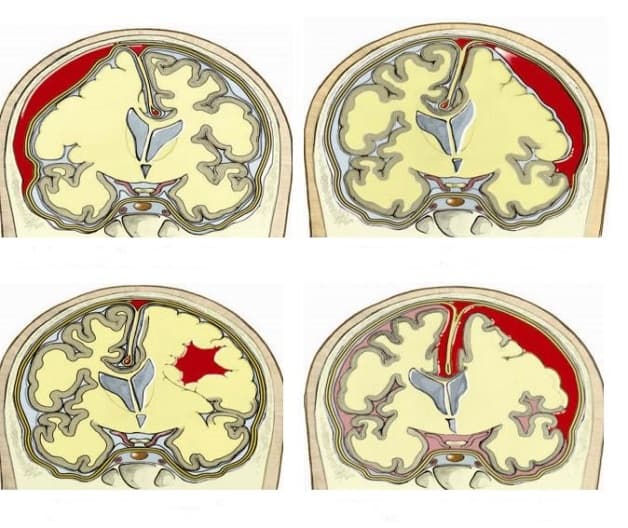

– Có khối choán chỗ ở bên trong sọ não: Có cả dấu hiệu trực tiếp (sự thay đổi tỷ trọng) và dấu hiệu gián tiếp (hiệu ứng khối choán chỗ) hoặc chỉ xuất hiện 1 trong 2. Dấu hiệu này có thể là tình trạng u não, ổ áp xe, ổ xuất huyết não, phù não hoặc các khối máu tụ nội sọ.

– Thay đổi tỷ trọng mô não: vùng tăng tỷ trọng (các ổ máu tụ, đám xuất huyết…), vùng giảm tỷ trọng (áp xe não, nhồi máu não, di căn ung thư), nốt vôi hóa (u não, u thần kinh đệm ít nhánh…), đồng tỷ trọng.